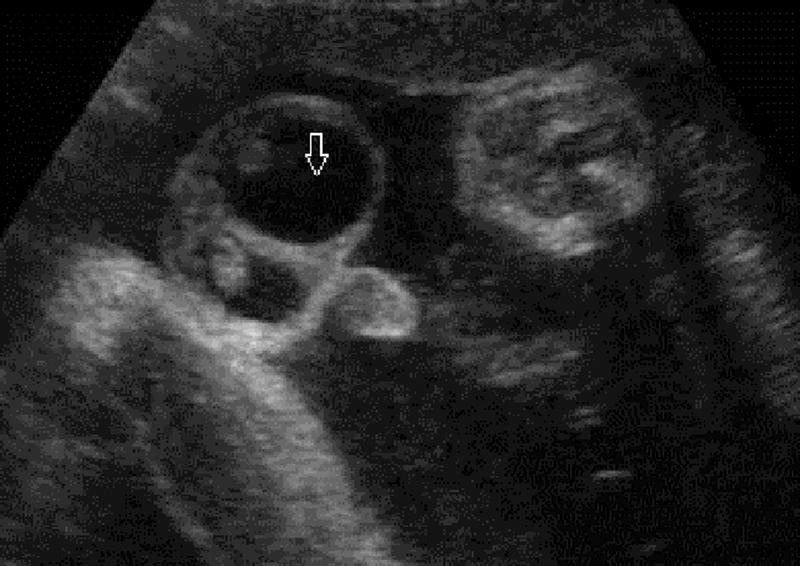

Gambar 1. Hidrokel antenatal, menunjukkan cairan pada scrotal sac dengan testis yang echogenic

Secara sonografis, hidrokel kongenital biasanya tampak sebagai kumpulan cairan anekhoik (hitam) sederhana yang mengelilingi aspek anterolateral testis. Sebagian besar kasus ini akan sembuh secara spontan sebelum usia dua tahun seiring dengan penutupan PPV yang tertunda. Oleh karena itu, penatalaksanaan pada populasi pediatrik sering kali bersifat konservatif dan observasional.